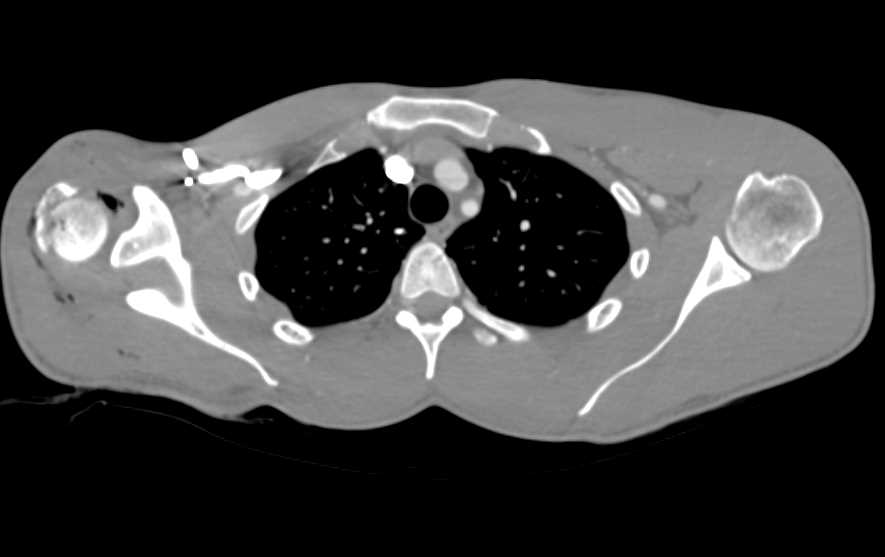

Hardware for Repair of the Tibia and Fibula Fractures